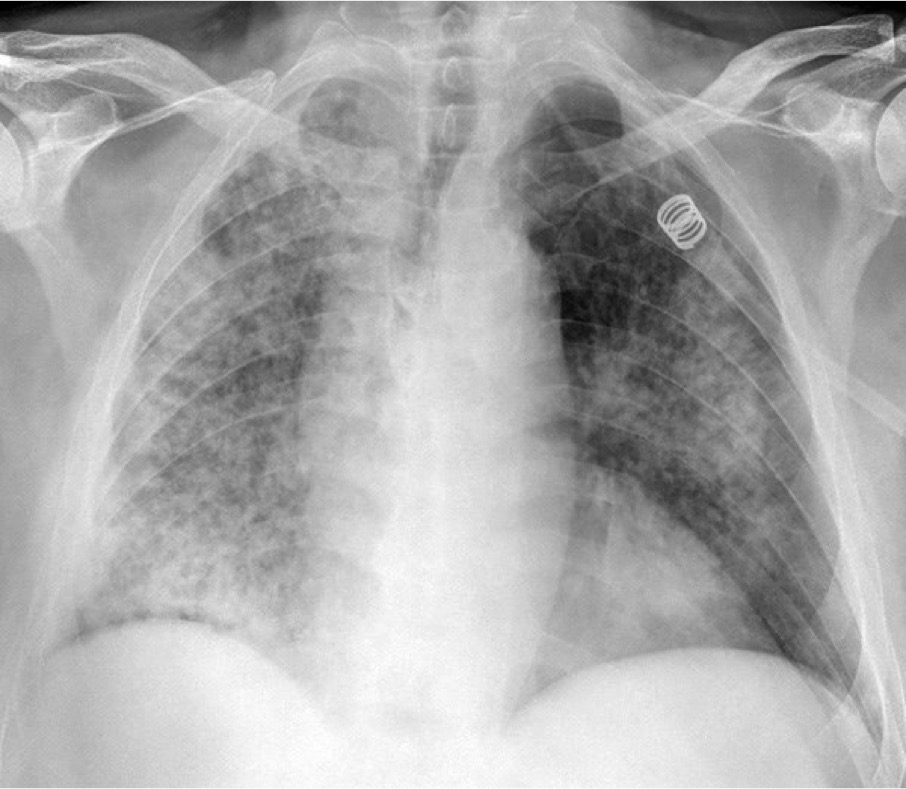

CASO: Febrícula y tos de 4 días de evolución.

Hallazgos:

- En la placa PA se observa una asimetría en los hilios pulmonares, el hilio izquierdo tiene una densidad aumentada.

- Tras examinar la placa lateral se observa un aumento de densidad en la columna que puede ser compatible con una condensación, es el signo de la desnificación vertebral.

SIGNO DE LA DENSIFICACIÓN VERTEBRAL: En la radiografía lateral normal, la densidad de la columna torácica tiende a disminuir desde la parte superior hasta el diafragma; la alteración de ese patrón por la presencia de una densidad superpuesta a la columna, indica la existencia de una consolidación pulmonar. Este signo adquiere especial valor cuando en la proyección posteroanterior la consolidación está oculta en el espacio retrocardíaco o en la base pulmonar.